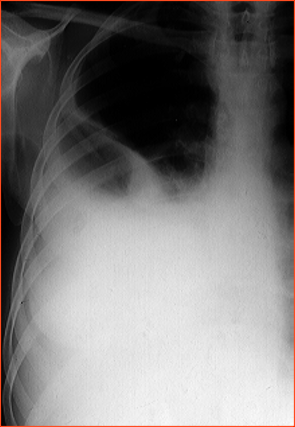

Rx toracică, incidență P-A

DESCRIERE:

la niv. întregului hemitorace stg → opacitate extinsă, nesistematizată, de intensitate mare, omogenă

caracter retractil → tracționează traheea și mediastinul de partea afectată

fără bronhogramă aerică

duce la micșorarea spațiilor intercostale

la niv. hemitoracelui controlateral → hipertransparență compensatorie (emfizem)

DX: atelectazie prin NBP central endobronșic (pe bronhia principală stg)

DD: pleurezie masivă → caracter expansiv